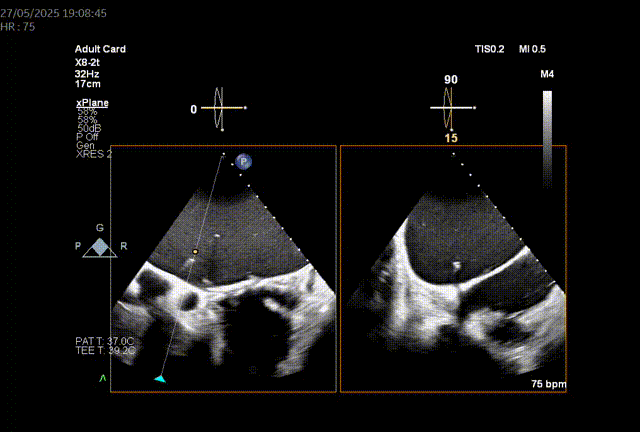

左房尺寸:长轴90.6mm,短轴79.2mm

由于二尖瓣环和主动脉瓣角度过大,若采取经心尖方式,同轴性不佳,且难以调整定位件,同样采取经房间隔方式。